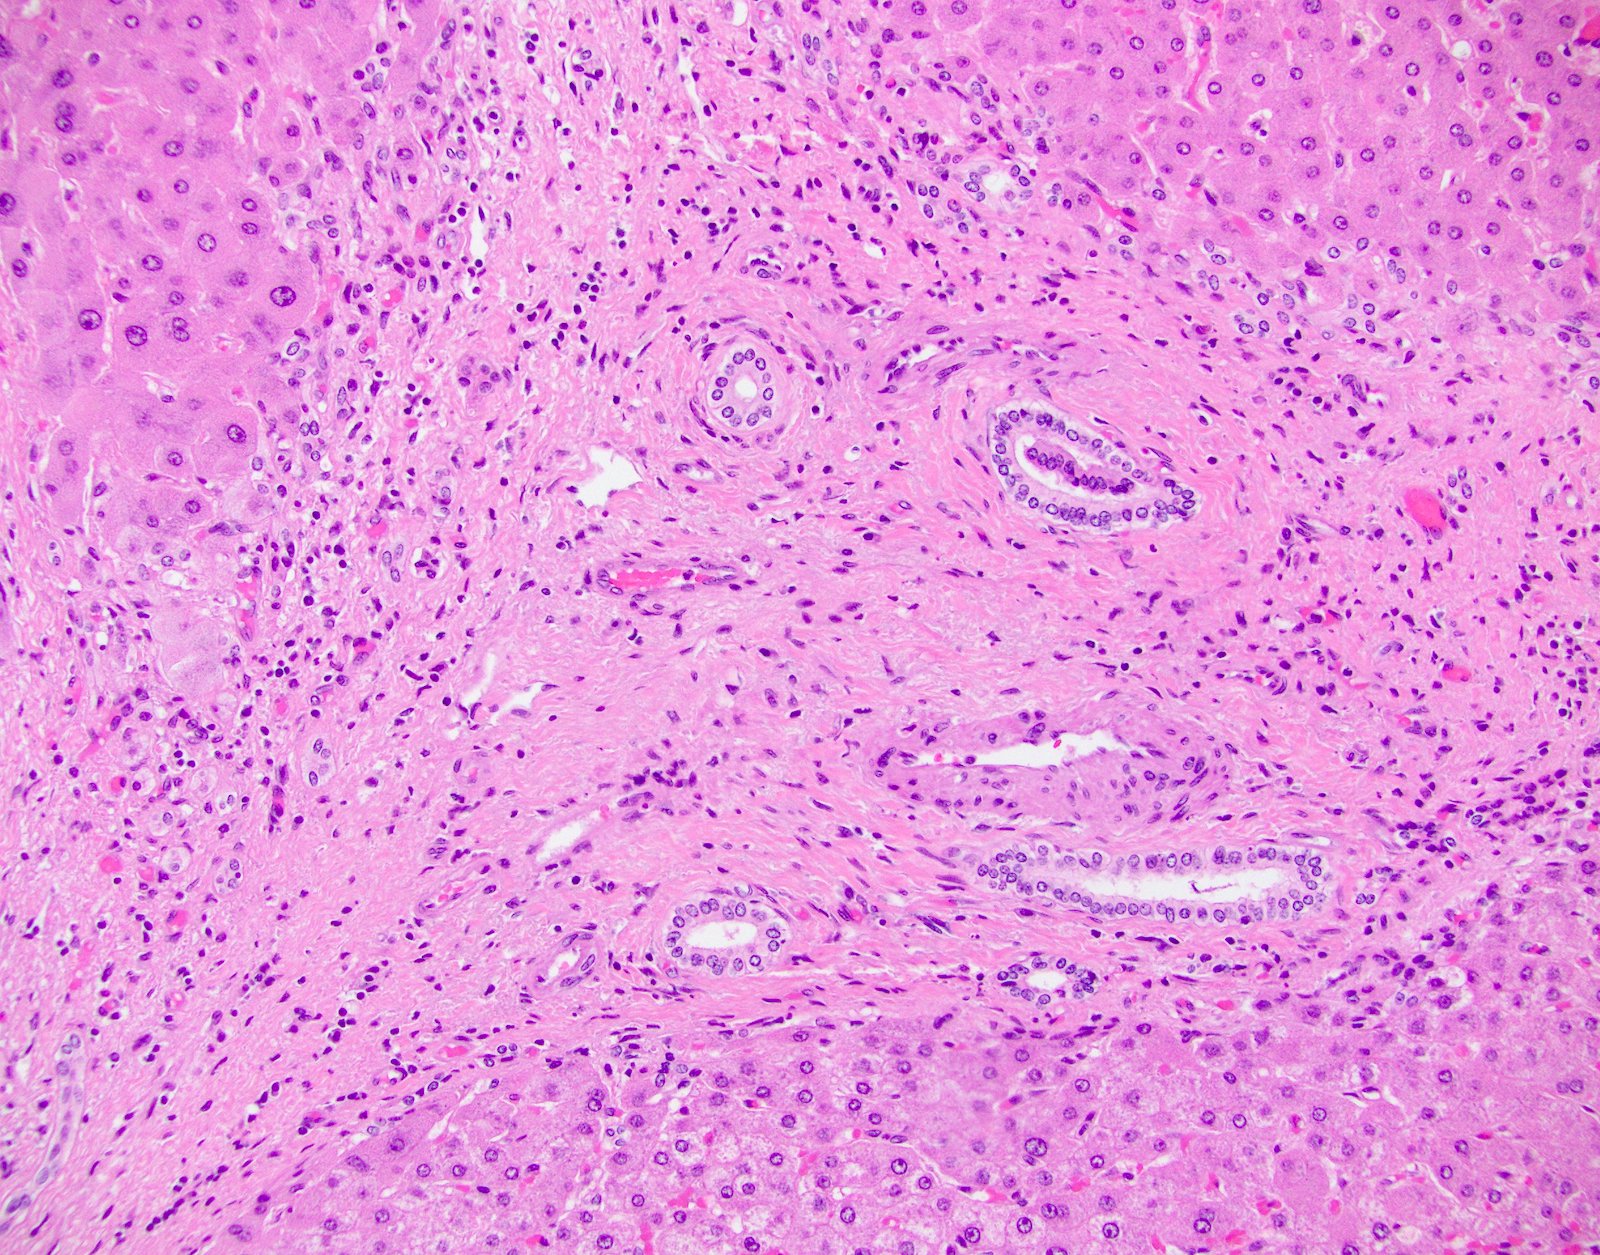

- Inflammation (Clin Transplant 2018;32:e13227, Liver Transpl 2016;22:1593, Liver Transpl 2018;24:897):

- Chronic hepatitis pattern of mononuclear inflammation with interface hepatitis or lobular and perivenular inflammation

- Perivenulitis

- Vascular changes (Pediatr Transplant 2018; 22:e13124, Am J Transplant 2018;18:1534):

- Obliterative portal venopathy with nodular regenerative hyperplasia-like changes

- Obliterative arteriopathy or isolated arterial "V" lesions (age inappropriate arterial fibrointimal hyperplasia with no T cell mediated rejection) with or without intimal inflammation arterial lesions are associated with subsequent T cell mediated rejection (TCMR), graft failure and C4d positivity; most C4d positive cases show additional histologic features encountered in cAMR such as portal and perivenular inflammation (rejection activity index / RAI 1 - 2) and at least moderate periportal, perivenular or sinusoidal fibrosis (Am J Transplant 2018;18:1534)

- Bile duct changes (Liver Transpl 2018;24:897):

- Biliary epithelial senescence and duct loss may be seen but at lower rates

- Distinct fibrosis patterns (Am J Transplant 2016;16:603, Transplantation 2017;101:2062, Clin Transplant 2018;32:e13227, Liver Transpl 2016;22:1593, Liver Transpl 2018;24:897):

- Dense acellular portal collagen deposition: portal collagenization

- Distinct subsinusoidal and perivenular fibrosis

- Focal nodular hyperplasia-like changes: usually without the map-like glutamine synthetase staining pattern or dystrophic vasculature usually seen in classic focal nodular hyperplasia lesions